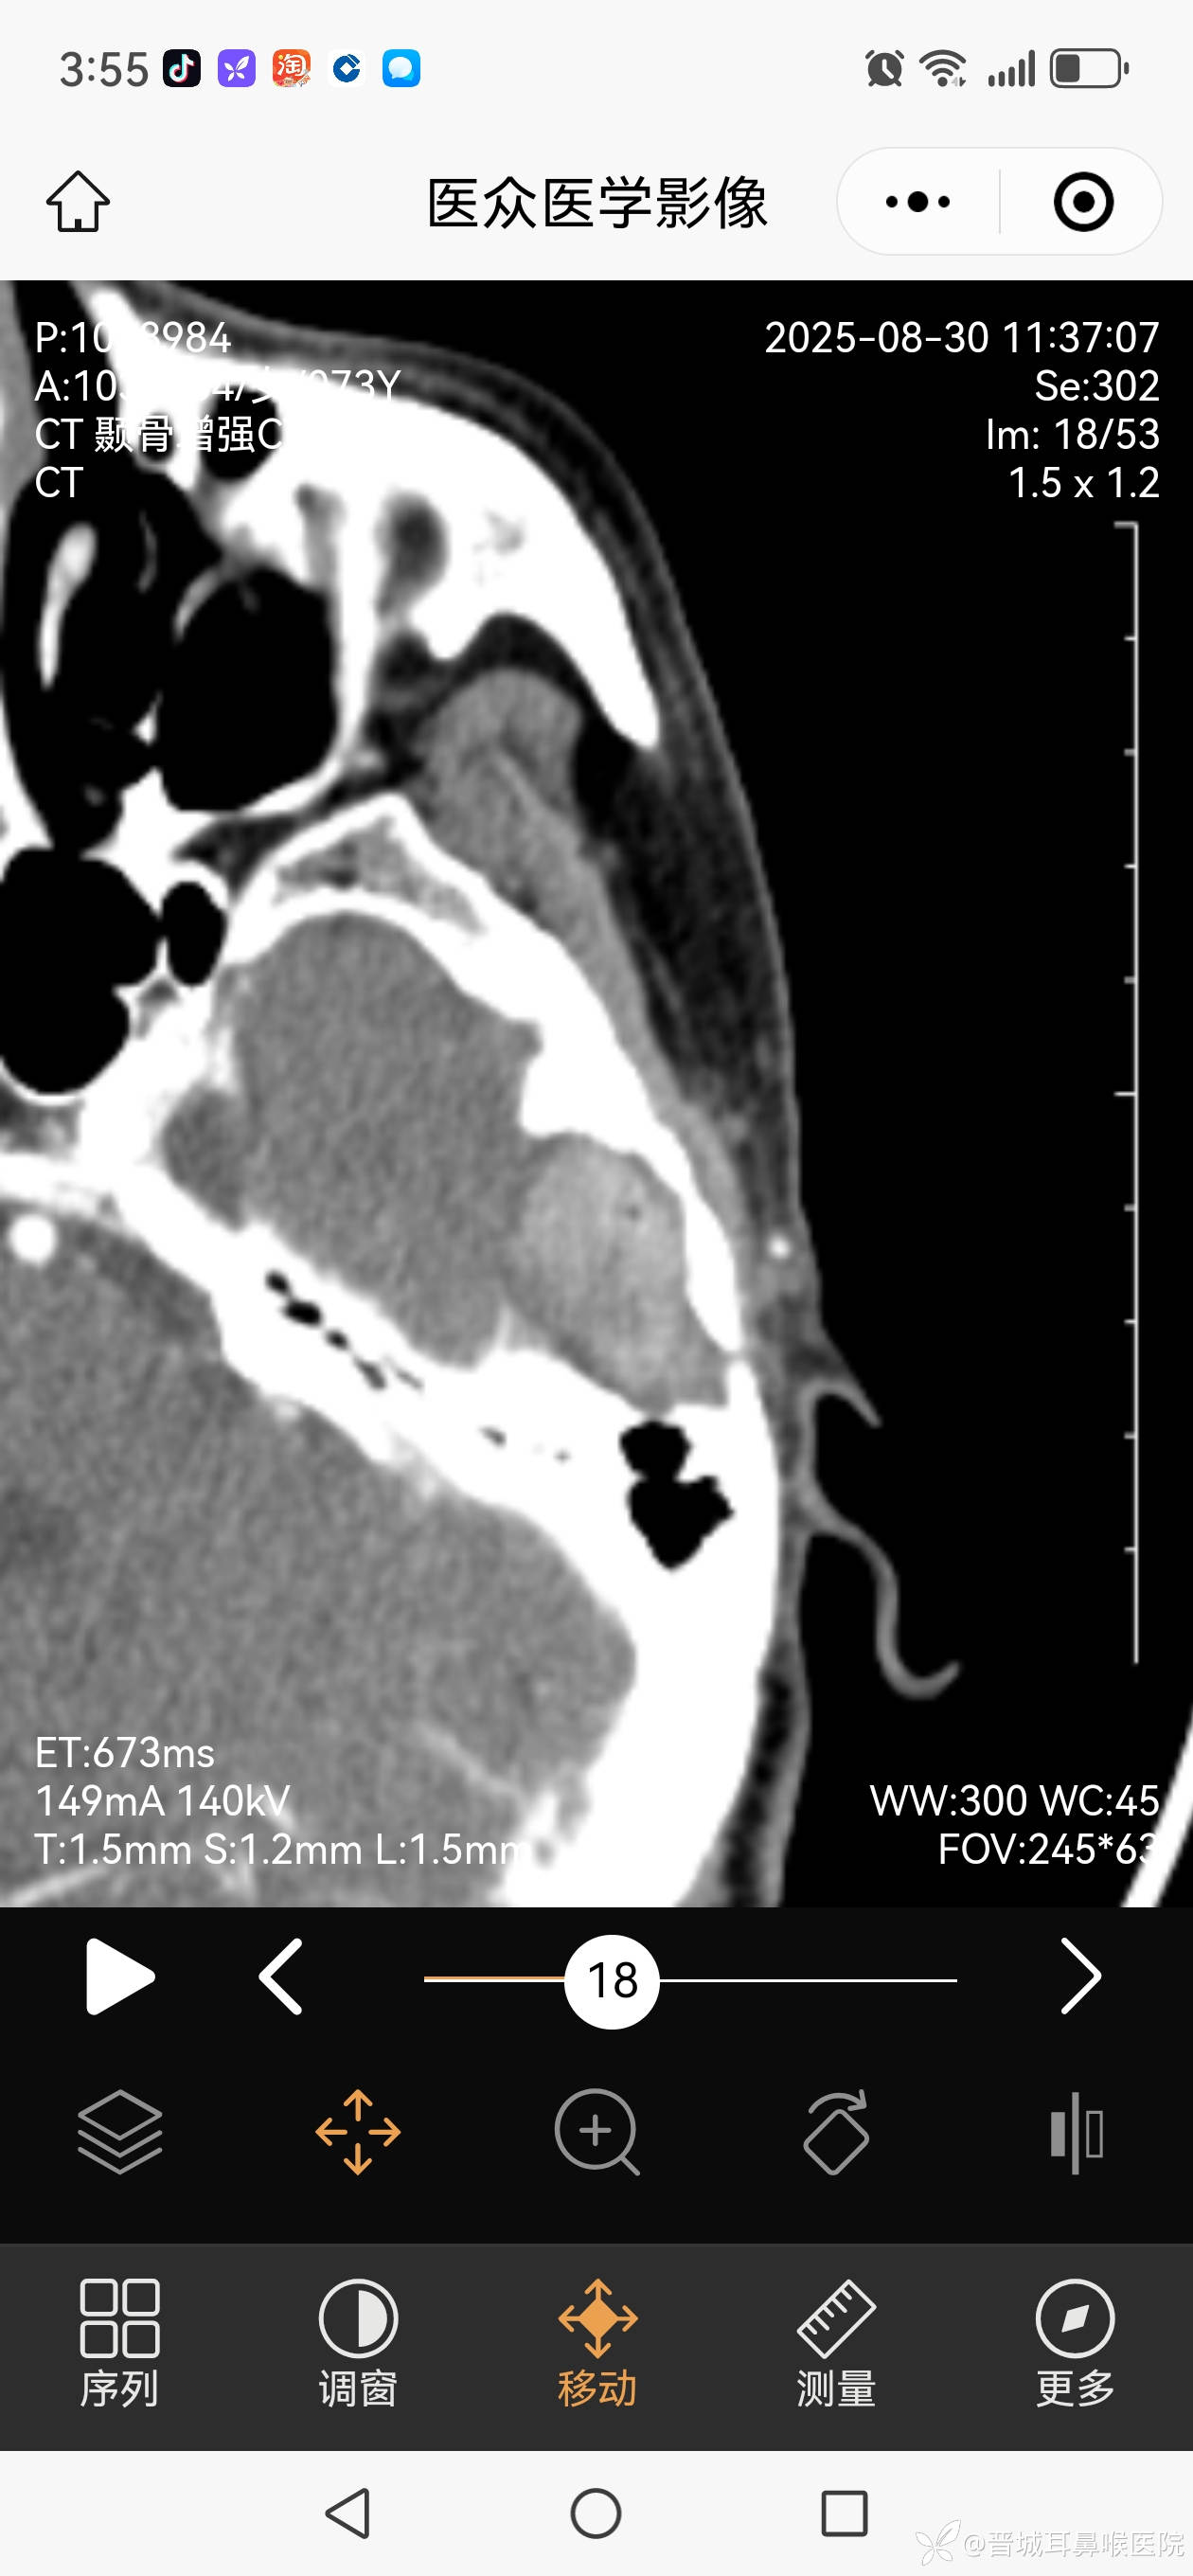

外耳道胆脂瘤不单破会后壁侵入乳突气房,更破坏前上壁,颞下颌关节囊暴露,在中颅窝形成比核桃大的胆脂瘤。